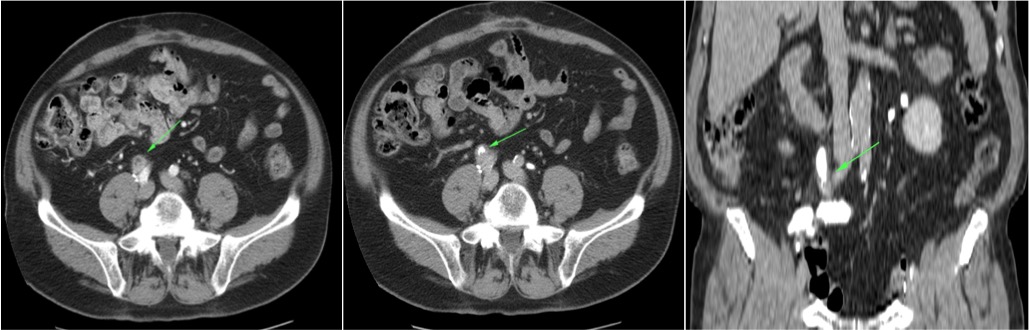

CASO CLÍNICO: Recopilatoción.

Paciente de 59 años con antecedentes personales de Cá de vejiga.

Se le realiza una Uro-Tc por seguimiento al año, aunque en esta ocasión el paciente refiere episodio de hematuria.

Se realiza nueva TC bifásico abdominopélvio y Uro TC.